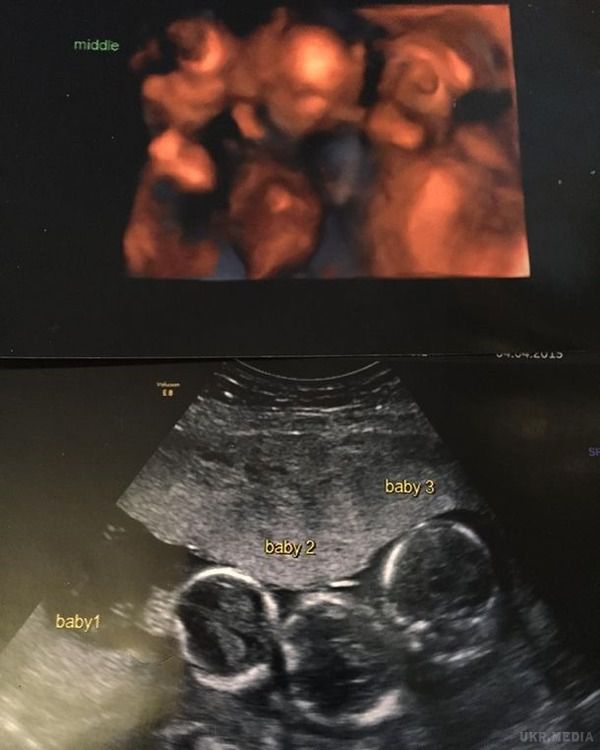

Майбутні батьки почали турбуватися. Вперше відправившись на УЗД, вони вже прокручували в голові всі найгірші варіанти.

Але лікар повідомила їм новину, яка на мить просто вибила їх з колії. Беккі очікувала трійню: «Це була шокуюча новина в моєму житті. За всю історію наших сімей в них ніколи не було трійнят — цього ми ніяк не очікували».